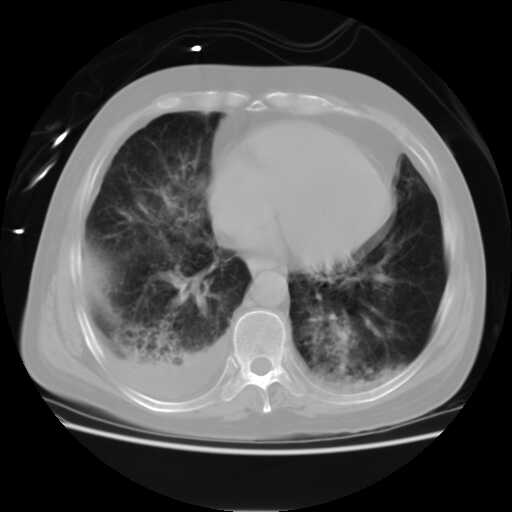

2008.5.16胸片

2008.8.17ct